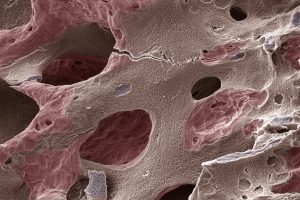

A hiperplasia prostática benigna (HPB) é uma condição comum que afeta homens a partir dos 40 anos, resultando no aumento da próstata e, consequentemente, na frequência urinária. Embora não seja câncer, seus efeitos podem impactar o sono e a qualidade de vida. O urologista Berthran Severo Garcia destaca que hábitos saudáveis podem retardar esse processo. A avaliação médica é crucial para diferenciar a HPB de condições mais graves, como o câncer de próstata, que pode ser assintomático em suas fases iniciais. Os sintomas urinários podem variar e, em casos mais severos, o tratamento pode incluir medicamentos ou cirurgia. O procedimento mais moderno, a enucleação a laser, oferece recuperação rápida e menos invasiva. Mantenha-se informado sobre saúde masculina e consulte um especialista regularmente para monitorar sua saúde prostática.

Hiperplasia Prostática Benigna: Entenda como afeta a saúde urinária dos homens

SEBASTIAN KAULITZKI/SCIENCE PHOTO LIBRARY/Getty Images